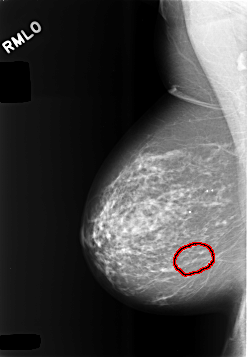

C_0473_1.RIGHT_MLO

FILE: C_0473_1.RIGHT_MLO.OVERLAY

TOTAL_ABNORMALITIES 1

ABNORMALITY 1

LESION_TYPE CALCIFICATION TYPE FINE_LINEAR_BRANCHING DISTRIBUTION LINEAR

ASSESSMENT 4

SUBTLETY 3

PATHOLOGY BENIGN

TOTAL_OUTLINES 1

BOUNDARY